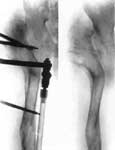

1.Врожденный вывих правого бедра, состояние после операции.

2.Операция Шанца-Илизарова с удлинением бедра.

3.Результат лечения.